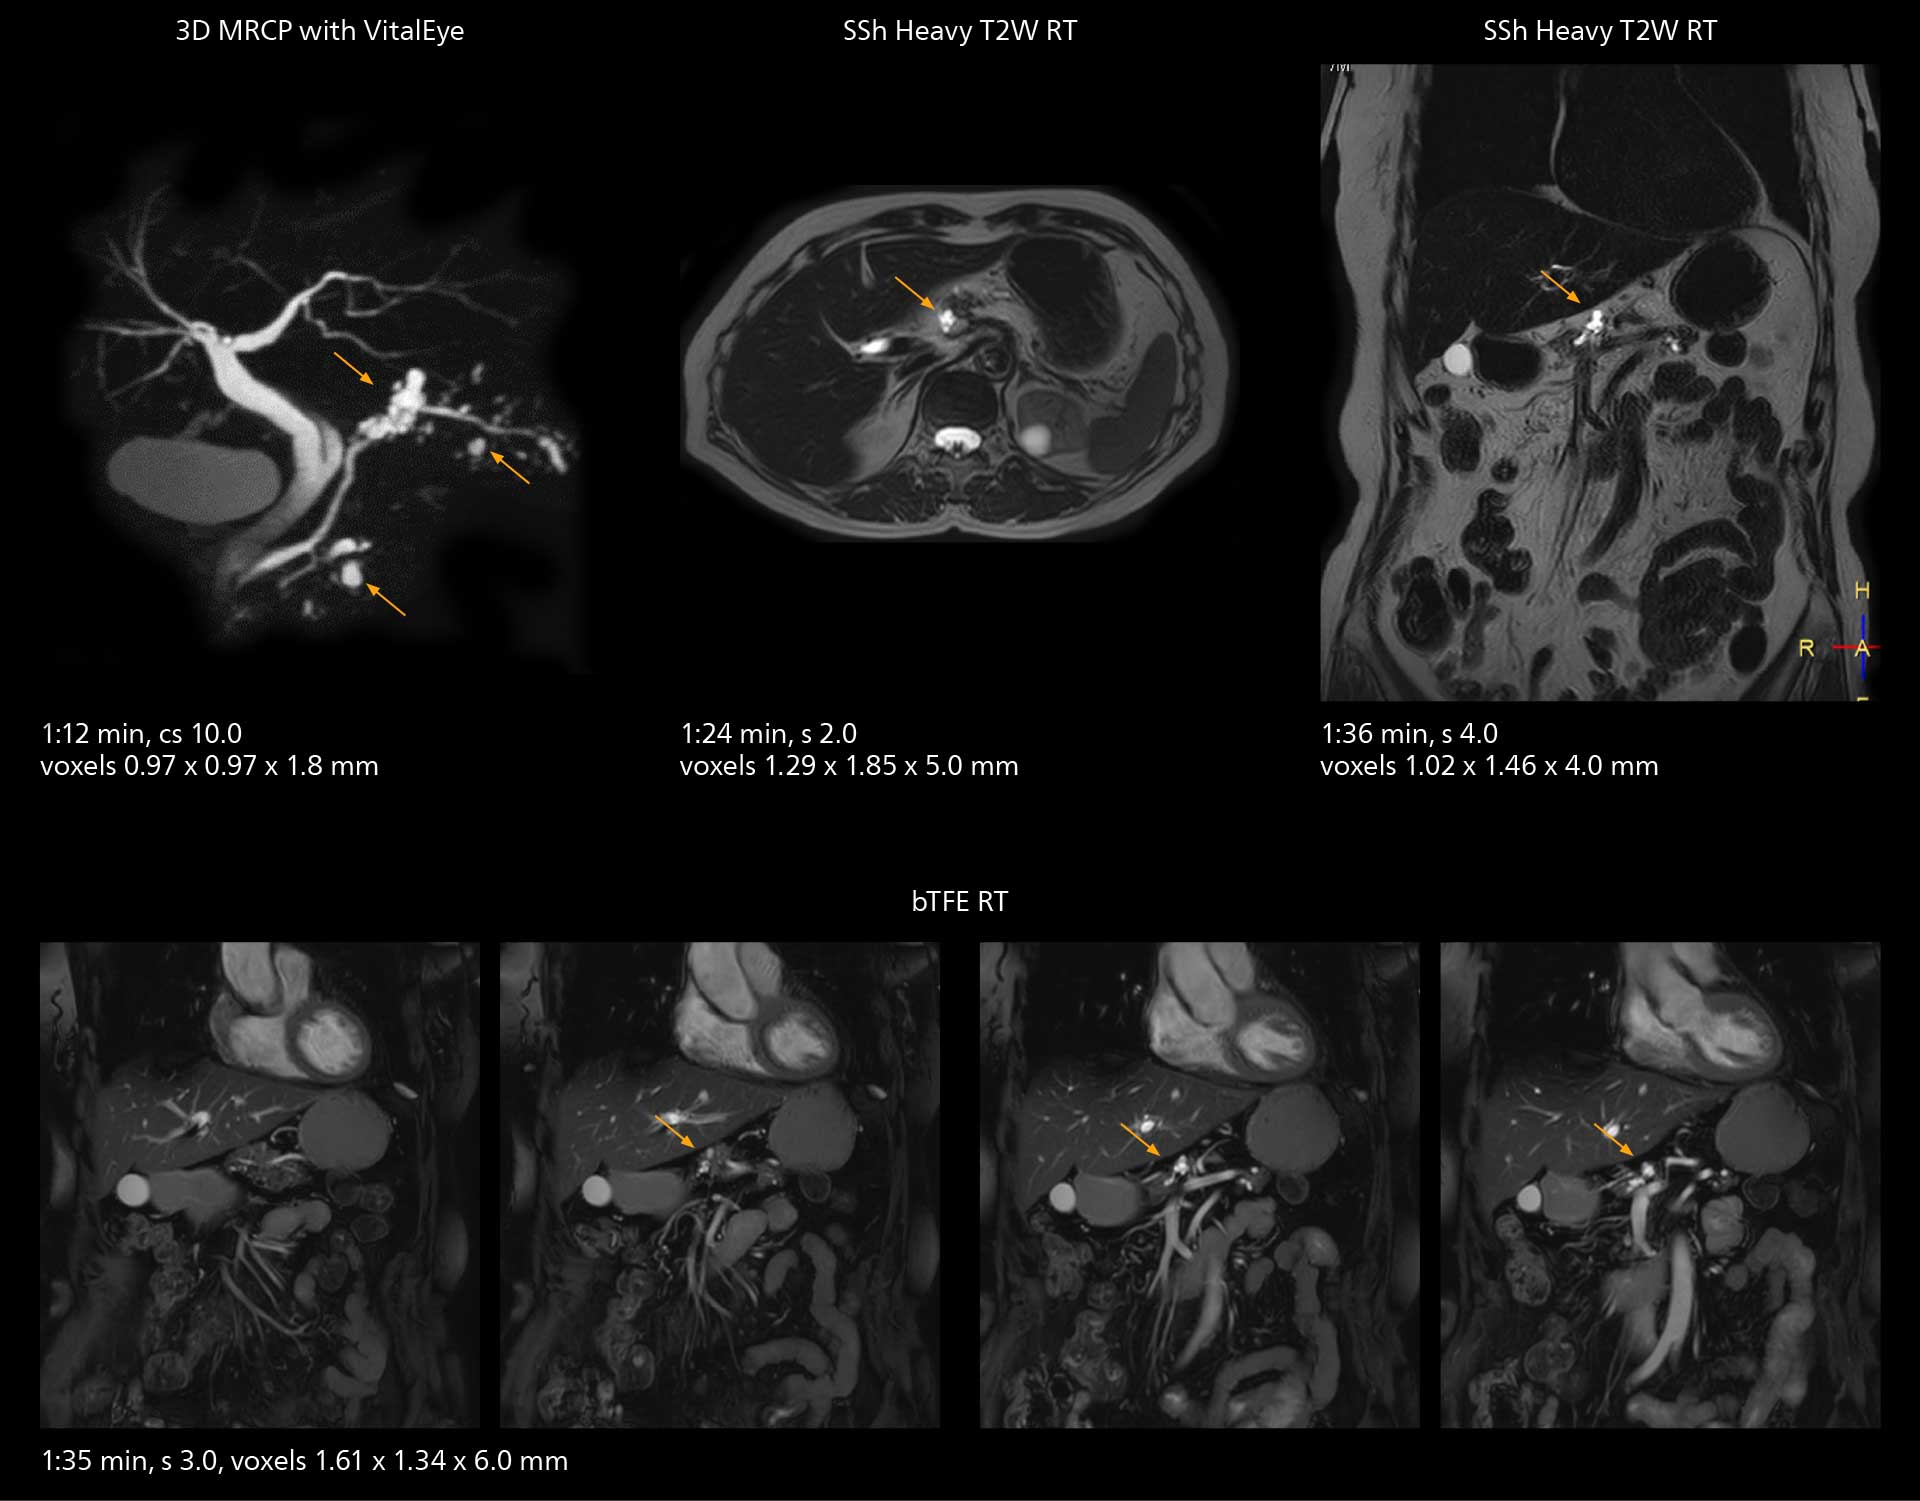

SmartPath to Elition X comes with Smart Workflow technologies that support technologists and can save them time. VitalEye for touchless patient sensing is one example. “The implementation of VitalEye respiratory synchronization has had a significant impact,” says MR technologist Yoshihiro Otsu, Chief of the Radiological Department. “It not only improves workflow, but it also has increased the quality of examinations. Particularly for the large number of MRCP examinations performed in this hospital, VitalEye has increased the possibility to obtain sharp images with less blurring. Clinicians here really appreciate this improvement in MRCP image quality.” The VitalScreen on the scanner has helped reduce the risk of patient misidentification. “It allows patient information to be viewed in the magnet room when standing next to the patient,” he says. “And the automated patient centering in the magnet is very useful as well.” Apart from reducing stress for technologists, Smart Workflow helps improve respiratory synchronization and reduce examination stress for the patient.

VitalEye has increased the possibility of obtaining sharp images with less blurring. Clinicians here really appreciate this improvement in MRCP image quality.”

Yoshihiro Otsu

With SmartPath to Elition X, the MRCP examinations at Sannodai Hospital benefit from VitalEye: respiratory synchronization is possible without respiratory belt positioning and image quality is excellent.